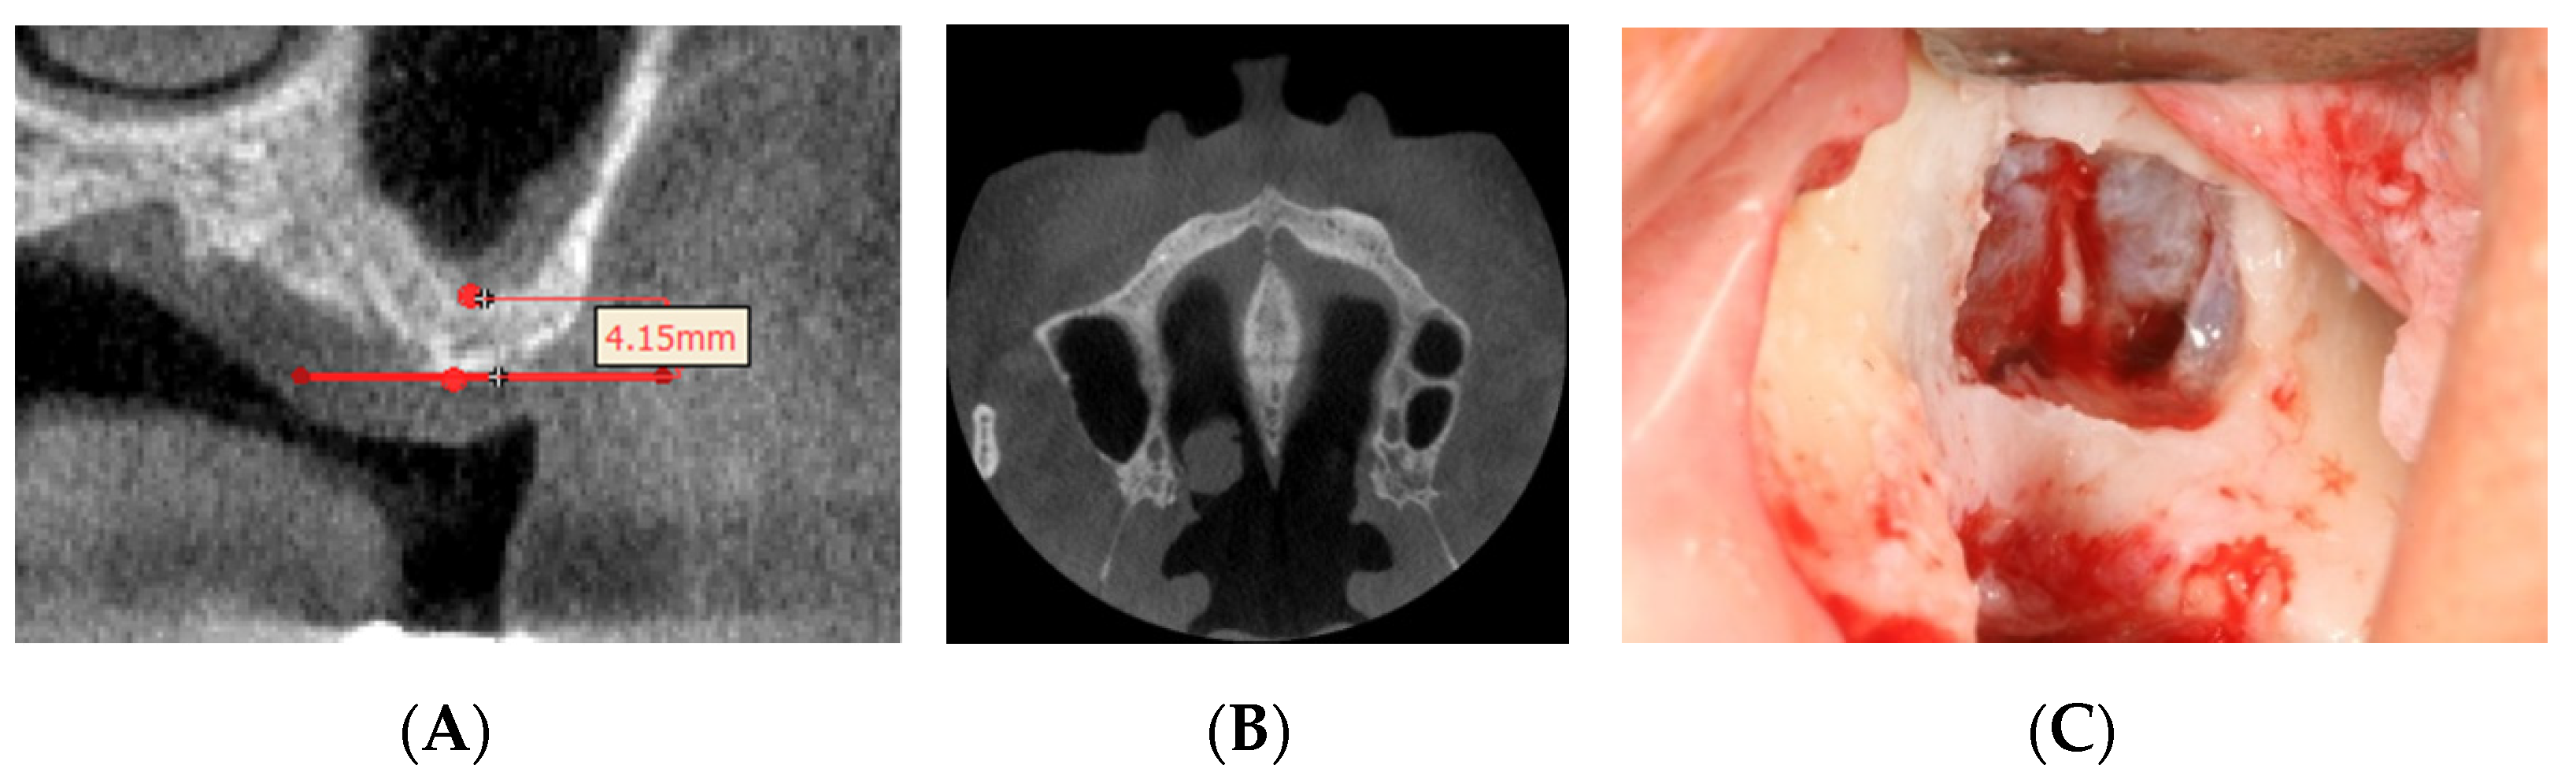

3.2. Lateral Wall Thickness of the Maxillary Sinus

| The Lateral Wall Thickness | |||

| Mean ± S.D. | Maximum | Minimum | |

| Thickness(mm) | 1.71 ± 0.55 | 3.93 | 0.74 |

| (Mean ± S.D.) | |||

| Gender | p-Value | ||

| Male | Female | ||

| Thickness(mm) | 1.76 ± 0.60 | 1.63 ± 0.44 | 0.830 |

4. Discussion